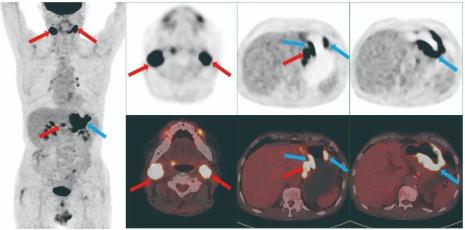

▲18F-FDG精准显示了王先生所患淋巴瘤的位置18F-FDG探针具有高灵敏度和特异度的优势,在肿瘤的诊断、分期、疗效评估和预后预测中具有重要的价值,超过90%的肿瘤在18F-FDG探针的探测下一览无余。

▲在部分肿瘤诊断上,68Ga-FAPI能点亮18F-FDG代谢不高的肿瘤,两者互补,共同“点亮”肿瘤,使其无处遁形其中68Ga-FAPI探针可用于靶向成纤维细胞活化蛋白(FAP)的显像,原因是FAP在多种肿瘤相关的成纤维细胞中过度表达。一些实体肿瘤,如乳腺癌、结肠癌和胰腺癌等,具有很强的促纤维增生反应的特性,使得肿瘤相关的成纤维细胞和细胞外纤维化明显增多。68Ga标记成纤维细胞活化蛋白特异性酶抑制剂(FAPI)作为分子探针,通过靶向肿瘤微环境中丰富的FAP可使肿瘤可视化。在18F-FDG摄取不高的肿瘤中,68Ga-FAPI可能会摄取高,例如对于有些复发性卵巢癌患者,医生通过18F-FDG很难判断病灶在哪儿,因为卵巢癌很容易出现腹膜转移,而肠道的生理性摄取会掩盖医生对病灶的观察,而通过68Ga-FAPI可以将病灶显示得更精准。18F-FDG和68Ga-FAPI两者互补,共同“点亮”肿瘤。